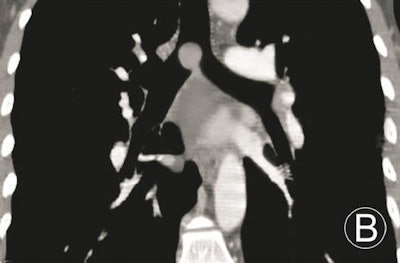

Regarding volume rendering, the group noted that it is an improvement over other postprocessing techniques such as shaded surface display, maximum-intensity projection, minimum-intensity projection, and tissue transition projection, which carry the disadvantage of losing large amounts of data in the final reconstruction.

Overall, volume rendering produces well-differentiated displays with good contrast resolution and differentiation of tissues, the authors wrote. It maintains spatial relationships from initial data with less loss of imaging information and also true 3D effects, and it allows the local magnification and rotation of images to examine tumors closely.

Volume-rendered images can handily demonstrate locations, morphologies of primary trachea and main bronchus tumors, and morphologies and extents of luminal stenoses, and it can measure the longitudinal involvements and distances between main bronchus tumors and trachea carinae. However, volume rendering can't display the internal features of tumors and extramural invasions, they noted.